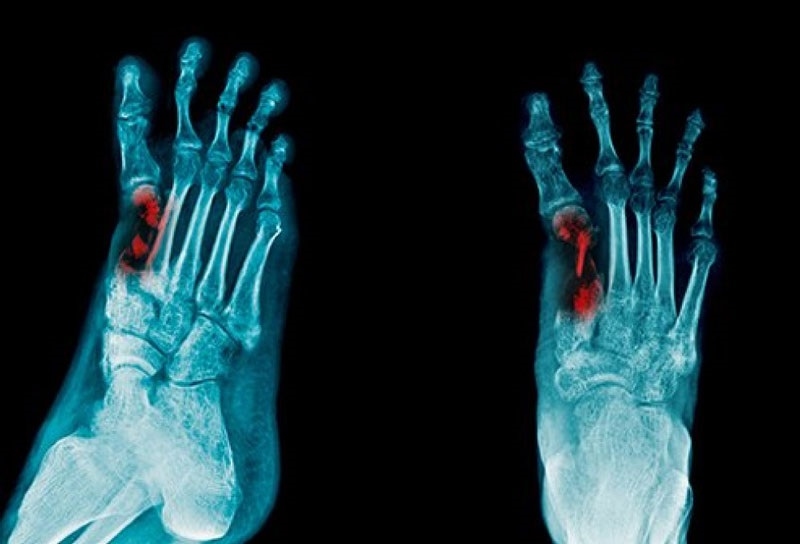

Khi xuất hiện các dấu hiệu nghi ngờ viêm tủy xương, người bệnh cần được thăm khám lâm sàng và thực hiện các danh mục cần thiết theo chỉ định của bác sĩ để kịp thời chẩn đoán và điều trị. Một trong những xét nghiệm hình ảnh đầu tiên thường được chỉ định là chụp X quang. Tuy nhiên, trong vòng 7 – 10 ngày đầu, hình ảnh X quang có thể chưa cho thấy rõ dấu hiệu viêm. Khi chụp lại sau khoảng 12 ngày, những tổn thương viêm xương mới bắt đầu hiện rõ.

Ngoài ra, bác sĩ có thể chỉ định chụp cắt lớp để quan sát chi tiết hơn những thay đổi ở mô mềm do viêm.

Tóm lại, tùy vào từng giai đoạn và đặc điểm của bệnh nhân, bác sĩ sẽ lựa chọn kỹ thuật phù hợp như X quang, MRI, CT scan hay xạ hình xương. Việc phối hợp chẩn đoán hình ảnh với lâm sàng và xét nghiệm là yếu tố quan trọng giúp đưa ra quyết định điều trị chính xác. Nếu bạn hoặc người thân có các dấu hiệu nghi ngờ viêm xương tủy như đau nhức xương kéo dài, sốt không rõ nguyên nhân, hoặc có tiền sử tiểu đường, chấn thương xương – hãy chủ động thăm khám sớm và thực hiện các chỉ định chẩn đoán hình ảnh cần thiết tại các cơ sở y tế uy tín!